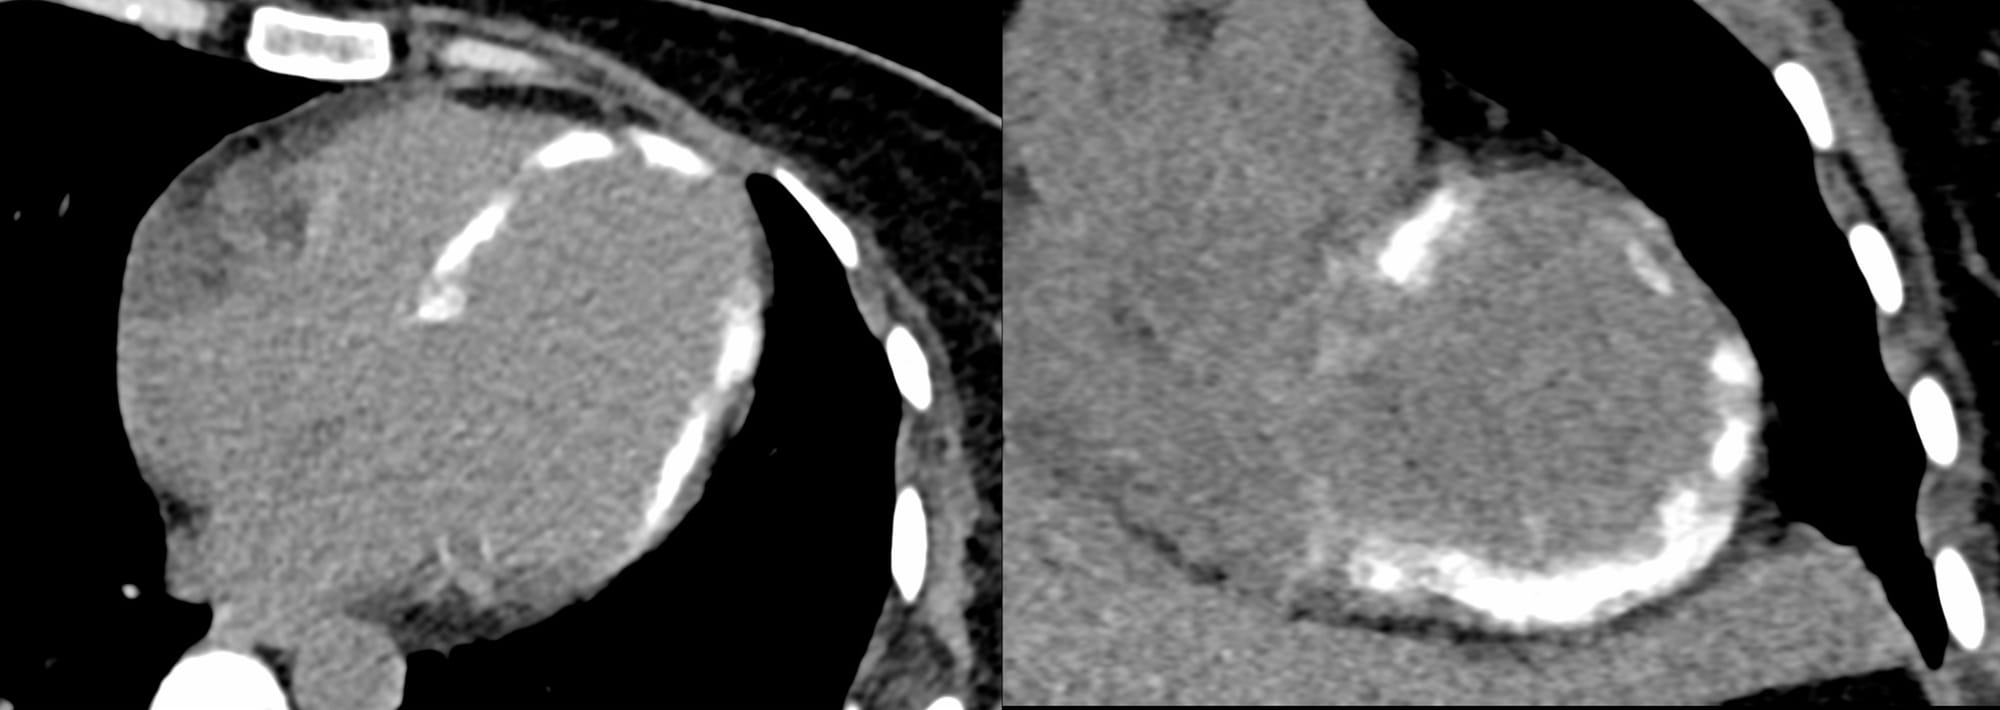

A 45-years old came for a chest and abdominal CT for abdominal complaints and this was found.

Diffuse myocardial calcification is unusual and the patient had a history of a near-death experience due to sepsis with multi-organ failure.